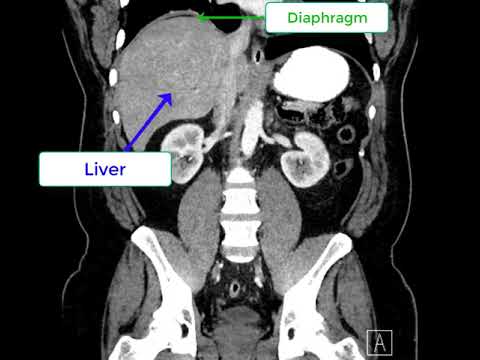

이 분은 78세의 사나이다. 만성 소화 불량으로 몇년 전부터 필자가 담당하는 분이라고. 2012년 담낭 담석이 하나 있고 담낭 절제를 하고 가슴이 아프다며 그 후에 관상 동맥 ct를 시행하고 약 50%관상 동맥의 협착이 있다고 했으나 그 이상의 조치는 하지 않았다. 역류성 식도염으로 투약하고 대체로 현재까지 잘 견디고 계신다. 최근 이 분의 다양한 사진을 검토하는 과정에서 위 사진처럼 횡격막과 간의 사이에 대장이 끼어 있는 것이 관찰됐으며 이 마직 막 사진에서는 그 부분의 대장에는 장의 작은 마비를 시사하는 수면(fluid level)를 가리키고 있혹시 이 분의 증상이 이른바 Chilaiditi증후군은 아닌지 의심스럽다. 이 분처럼 대장이 횡격막과 간의 사이에 끼는 현상을 Chilaiditissign. 이것이 확실히 증상을 부를 확인되면 Chilaiditi증후군으로 진단한다. 그러나 이 병은 감염이 매우 어려운 증상도 다양하다. 이 병은 19010년에 그리스의 방사선 의사인 Dimitrios Chilaiditi가 처음 기술했다. 뚜렷한 증상은 오른쪽 위 복부가 아프지만 다른 병이 설명할 수 없고 이런 현상을 보이면 이 병을 의심한다. 그러나 대장이 이 사이에 끼어 보이는 경우는 비교적 적지 않아 만약 간 경변증이 심하면 간이 위축되고 이런 가능성이 있다고 불리는 이 현상을 보이면 간 질환을 의심하고 보는 정도였다 만약 앞으로 이런 현상을 보이는 분들을 보면 관심을 갖고 검토할 필요가 있다고 생각한다.